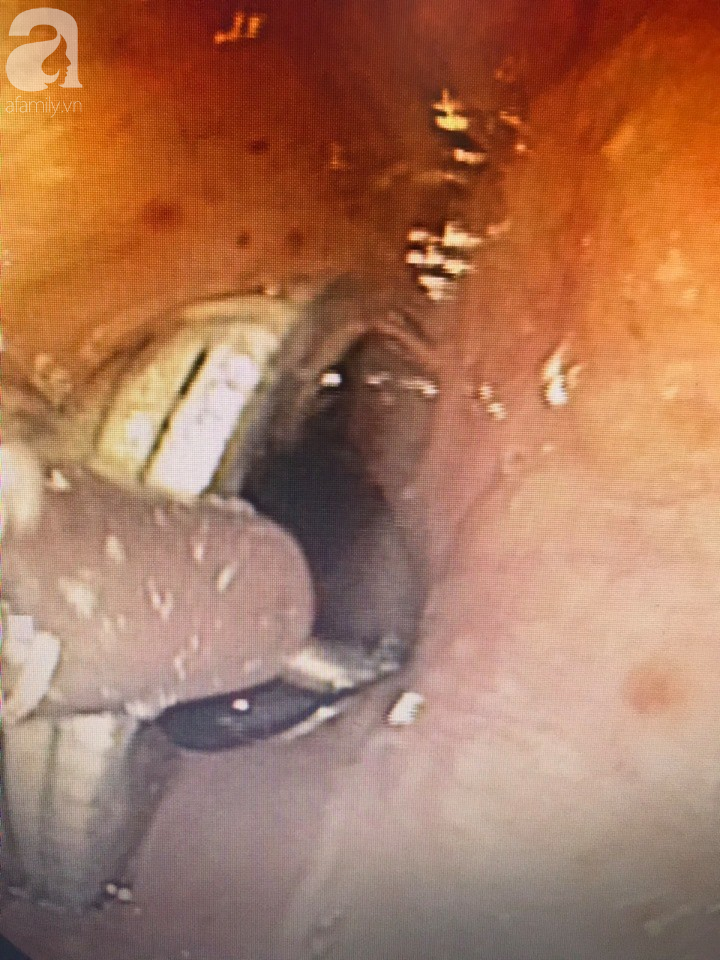

Ngay lập tức, bé được thực hiện nội soi cấp cứu có tiền mê. Các bác sĩ nhanh chóng kiểm tra thấy dị vật là kim loại hình tròn đường kính 20 mm, ở giữa có trục và kim loại nhô ra ngoài sắc nhọn cắm vào 1/3 thực quản trên của bé trai.

Sau khi thực hiện nội soi gắp dị vật, sức khỏe của bé trai đã ổn định.